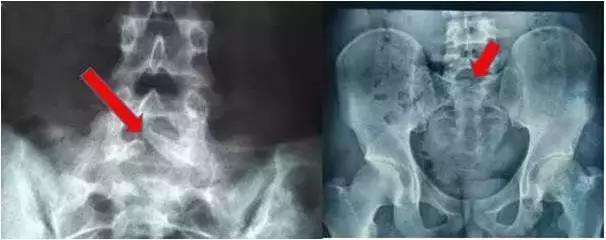

骶1隐裂图片

骶骨1隐裂图片

腰骶椎隐裂图片

骶椎隐裂x线图片

骶椎隐裂ct片图解图片